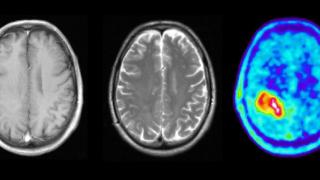

Acudió a urgencias pero en la sala de espera volvieron a aparecer las convulsiones. Al despertarse, se encontraba en una camilla desde la que escuchó el diagnóstico: glioma de bajo grado, un tumor cerebral del que aparecen unos 1.000 nuevos pacientes al año en España.

Además, estos tumores no se curan por completo con la cirugía y pueden volver. Cada seis meses José Luis se somete a una revisión en la que, a través de una resonancia magnética, se observa que el tumor siga estable.